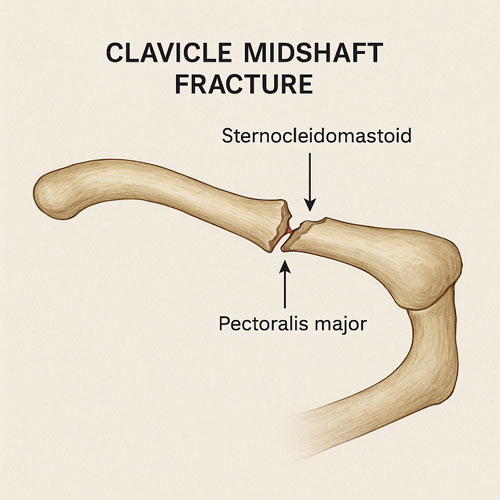

شکستگی وسط ترقوه

حدود ۸۰٪ شکستگیها در بخش میانی ترقوه (midshaft) اتفاق میافتد، زیرا این قسمت نازکتر و نیروهای مکانیکی بیشتری را تحمل میکند.